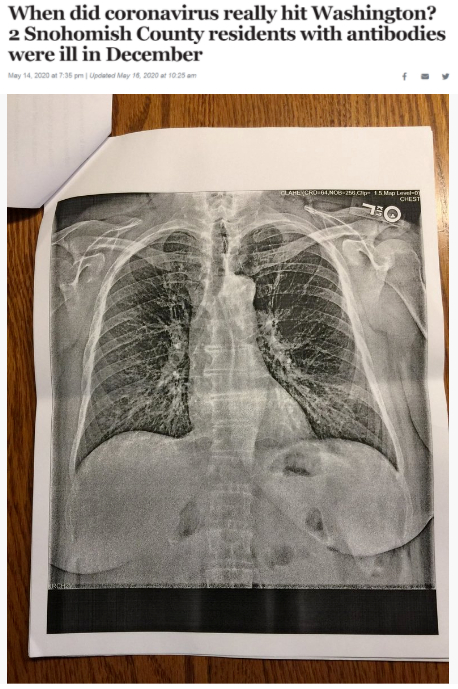

据《西雅图时报》去年5月14日报道,华盛顿州斯诺霍米什县的两位居民在2019年12月出现类似新冠肺炎的症状,之后对他们的新冠病毒抗体检测呈阳性反应。这一结果表明,新冠病毒可能比想象中更早在当地出现。

△《西雅图时报》报道截图(题图中的X光片显示其中一位斯诺霍米什县居民的肺部“过度充气”并出现“线性混浊”。医生认为,这可能是叠加上呼吸道肺部感染的表现。)